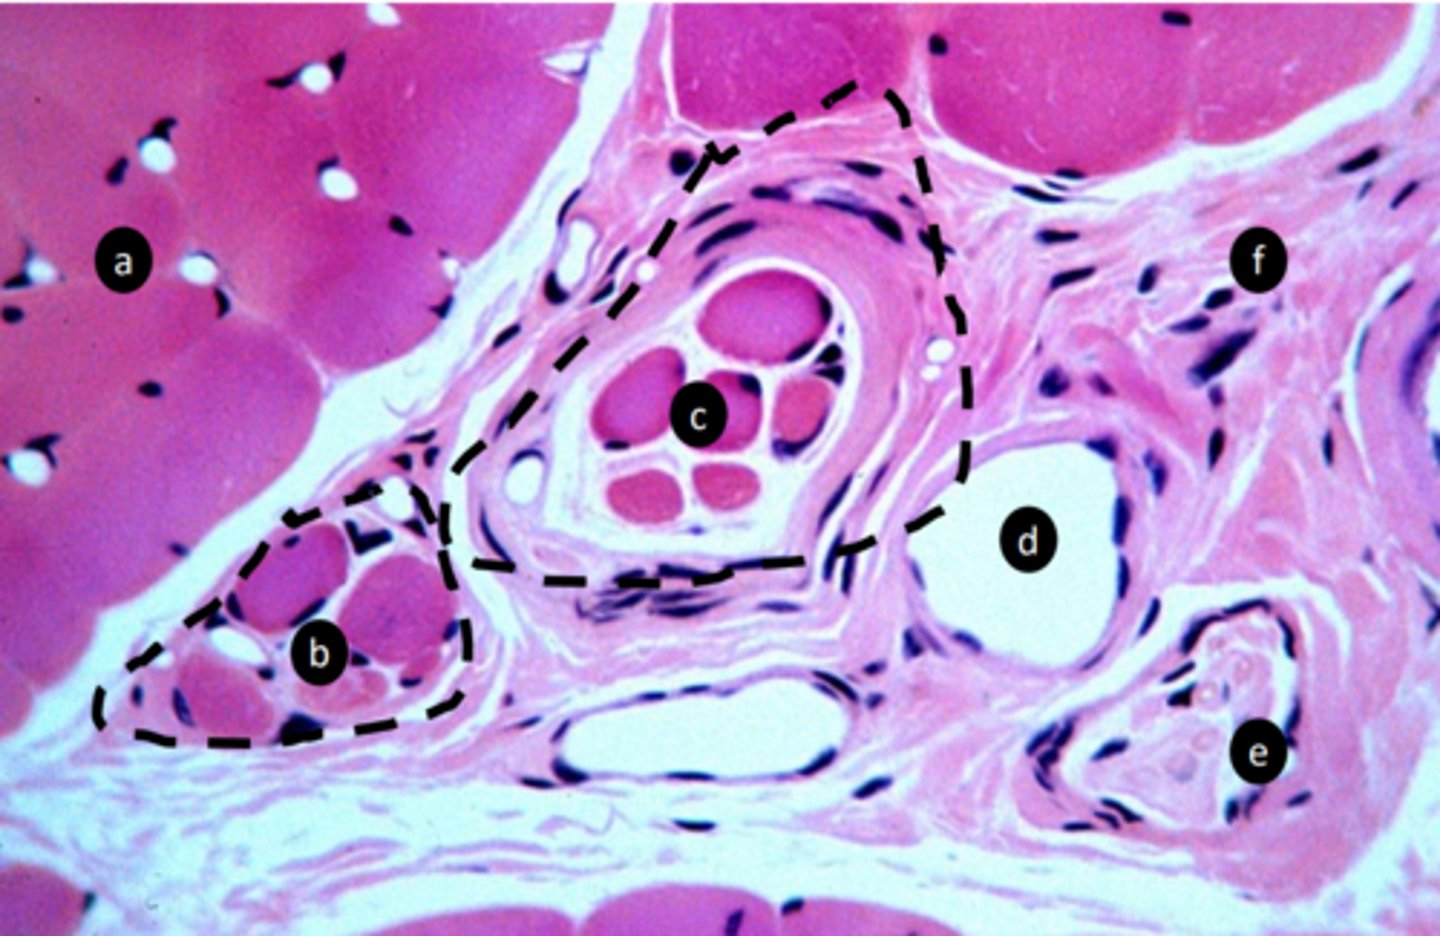

extrafusal myofibers

a: specific tissue type

<p>a: specific tissue type</p>

intrafusal muscle fiber

b: specific tissue type

<p>b: specific tissue type</p>

intrafusal muscle fiber (muscle spindle)

c: specific tissue type

<p>c: specific tissue type</p>

stretch receptor, proprioception: detect length and velocity

function of c?

<p>function of c?</p>

vein

e: structure

<p>e: structure</p>

nerve fibers

f: structure

<p>f: structure</p>